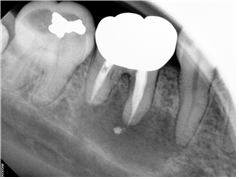

2023. 02. 02 : 재신경치료

우측 하악 낭종이 있으며, 우리한 증상이 10일 정도 지속되어 내원하셨습니다. 기존 신경치료된 치아가 원인으로 보여집니다. 치아 뿌리 하방에 2 cm 정도의 병소가 확인됩니다.

이럴 경우, 생각할 수 있는 게 1) 발치 2) 재신경치료입니다. 발치하고 임플란트하면 간단하고 확실할 순 있겠지만, 치아를 살리는 의미가 더 크겠지요. 다행히 환자분도 살리는 치료를 원하셨고, 결과가 나쁠 수도 있으나 재신경치료를 시행하셨습니다.

다행히 재신경치료는 잘 진행되었고, 신경관 3개 모두 잘 제거하고 소독을 시행하였습니다.